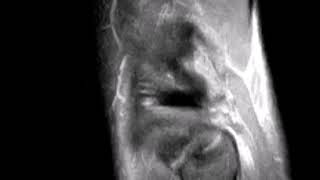

Pcl Tear Radiology Video indir